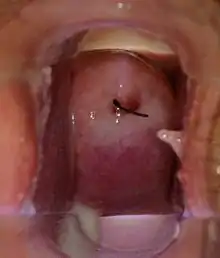

| Medical speculum exam shows normal vagina and cervix with normal milky white vaginal discharge on the vaginal walls, cervix, and pooled in the posterior vaginal fornix (IUD strings visible at opening of cervix) | |

Normal vaginal discharge is clear, white, or off-white.[1] The consistency can range from milky to clumpy, and odor is typically mild to non-existent.[1] The majority of the discharge pools in the deepest portion of the vagina (the posterior fornix)[3] and exits the body over the course of a day with the force of gravity.[1][4] A typical reproductive-age woman produces 1.5 grams (half to one teaspoon) of vaginal discharge every day.[1]

Upon the diagnosis of vaginitis, a speculum exam is performed to evaluate the vagina, vaginal discharge, and the cervix. The physician will insert the speculum into the vagina while the patient lies on their back to exam for foreign bodies, vaginal warts, inflammation, as well as rashes/bruises. A sample of the vaginal discharge is then collected using a cotton-swab and tested for pH and under microscopy.[18] The most common causes of pathological vaginal discharge in adolescents and adults are described below.